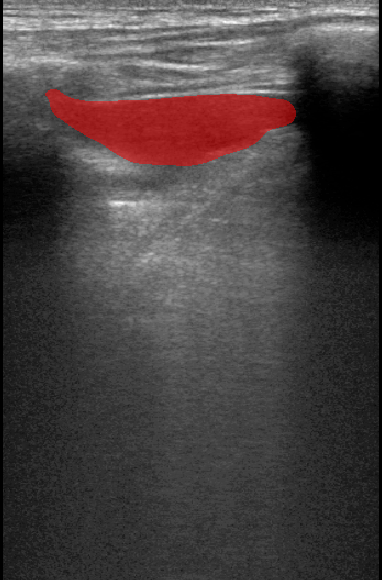

A total of 143 images were acquired from 59 patients. The images were obtained at the left and right PLAPS (PosteroLateral Alveolar and/or Pleural Syndrome) and subcostal views [4] with linear array and curved array (abdominal) ultrasound probes. The data were split according to the use of these probes into two datasets of 51 and 92 images, respectively for linear array and curved array. We denote these datasets as Dataset A (linear array) and Dataset B (curved array). All images were annotated at the time of acquisition to measure the extent of the effusion. These annotations consisted of small crosses at the top and bottom of the deepest area of effusion. See Figure 1 (left column) for example images.

Before being used for training and evaluating the models, each image was automatically cropped using a rectangular/cone mask to remove non-imaging content. Next, we applied an inpainting text algorithm using keras-ocr followed by template matching and edge detection algorithms from opencv to remove the annotations that were added to the images to measure the effusion. Examples of the outputs of this preprocessing are shown in Figure 1 (centre column).

All images in both datasets were manually segmented using the ITK-SNAP software [14] (www.itksnap.org) by a trained observer. Examples of ground truth segmentations are shown in Figure 1 (right column). These segmentations acted as ground truths for training and evaluating the proposed models. Additionally, a second trained observer performed independent segmentations of subsets of 10 random images each from the two datasets. These were used to compute an estimate of inter-observer variability in the manual segmentation process.

Qualitative prediction results of the two proposed models (baseline nnU-Net and nnU-Net with coordinate convolutions) on the two datasets are shown in Figure 2. Tables 1 and 2 summarise the quantitative performances in terms of DSC and area statistics. Histograms of the DSC values are shown in Figure 3. The median DSCs between the manual segmentations on the subsets of 10 images (i.e. the estimates of inter-observer variability) are also shown in Table 1.

It can be seen that, despite having fewer images, the baseline model for Dataset A obtained a higher median DSC than the model for Dataset B. For Dataset A the coordinate convolution model improved the DSC and reduced the area error and bias. In two-tailed Wilcoxon signed rank tests (0.05 significance) the difference between the baseline DSC and that of the coordinate convolution model was found to be statistically significant for Dataset A () but there was no statistically significant difference for Dataset B (). Interestingly, for both Dataset A and Dataset B, both the baseline and coordinate convolution models performed better than the estimate of inter-observer variability. However, we note that the inter-observer variability is quite high (i.e. median DSCs of 0.78 and 0.71), likely reflecting the difficulty and partly subjective nature of the effusion segmentation task. Therefore, it seems likely that the deep learning models are learning to segment effusion in the style of the main observer, which may not always be consistent with the second observer. In addition, the histograms shown in Figure 3 suggest that there are a significant number of failure cases in the outputs of both models (although fewer for the coordinate convolution model for Dataset A), again reflecting the difficulty of the task.

Rows 1-2: Dataset A. Rows 3-4: Dataset B.